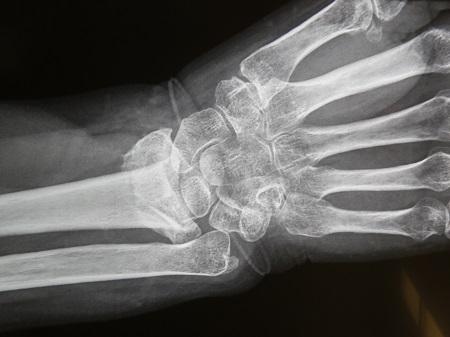

Η ολική αρθροπλαστική καρπού αποτελεί ένα πολύ ισχυρό όπλο στην φαρέτρα των ορθοπεδικών, καθώς οι μέχρι χτες λύσεις, για την κατεστραμμένη άρθρωση του καρπού (από διάφορες αιτίες), ήταν η μόνιμη ολική αρθρόδεση του σε ενεργούς χειρώνακτες ή η αφαίρεση τού εγγύς στοίχου (row carpectomy) σε γυναίκες κυρίως μειωμένων λειτουργικών απαιτήσεων. Οι επεμβάσεις αυτές (μόνιμη αρθροδεσία με πλακόβιδο και εγγύς καρπεκτομή ) παρουσίαζαν όμως σοβαρά λειτουργικά προβλήματα στις κινήσεις του χεριού.

Σύμφωνα με τον κ Ιγνατιάδη «η αρθροπλαστική καρπού, και ιδιαίτερα η τύπου “freedom” παρουσιάζει το σοβαρό πλεονέκτημα απέναντι στην αρθροδεσία ότι διατηρείται η κίνηση του καρπού, ενώ στην αρθροδεσία ναι μεν εξαλείφεται ο πόνος και διατηρείτο η ισχύς, πλην όμως καταργούνταν εντελώς η έκταση-κάμψη του καρπού, στη δε εγγύς καρπεκτομή είχαμε μεν κίνηση αλλά υπήρχε σχετική αστάθεια και έλλειψη ισχύος».